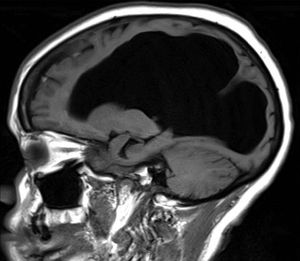

A) Cerebral aqueduct stenosis B) Meningitis C) Alzheimer's disease D) Traumatic brain injury